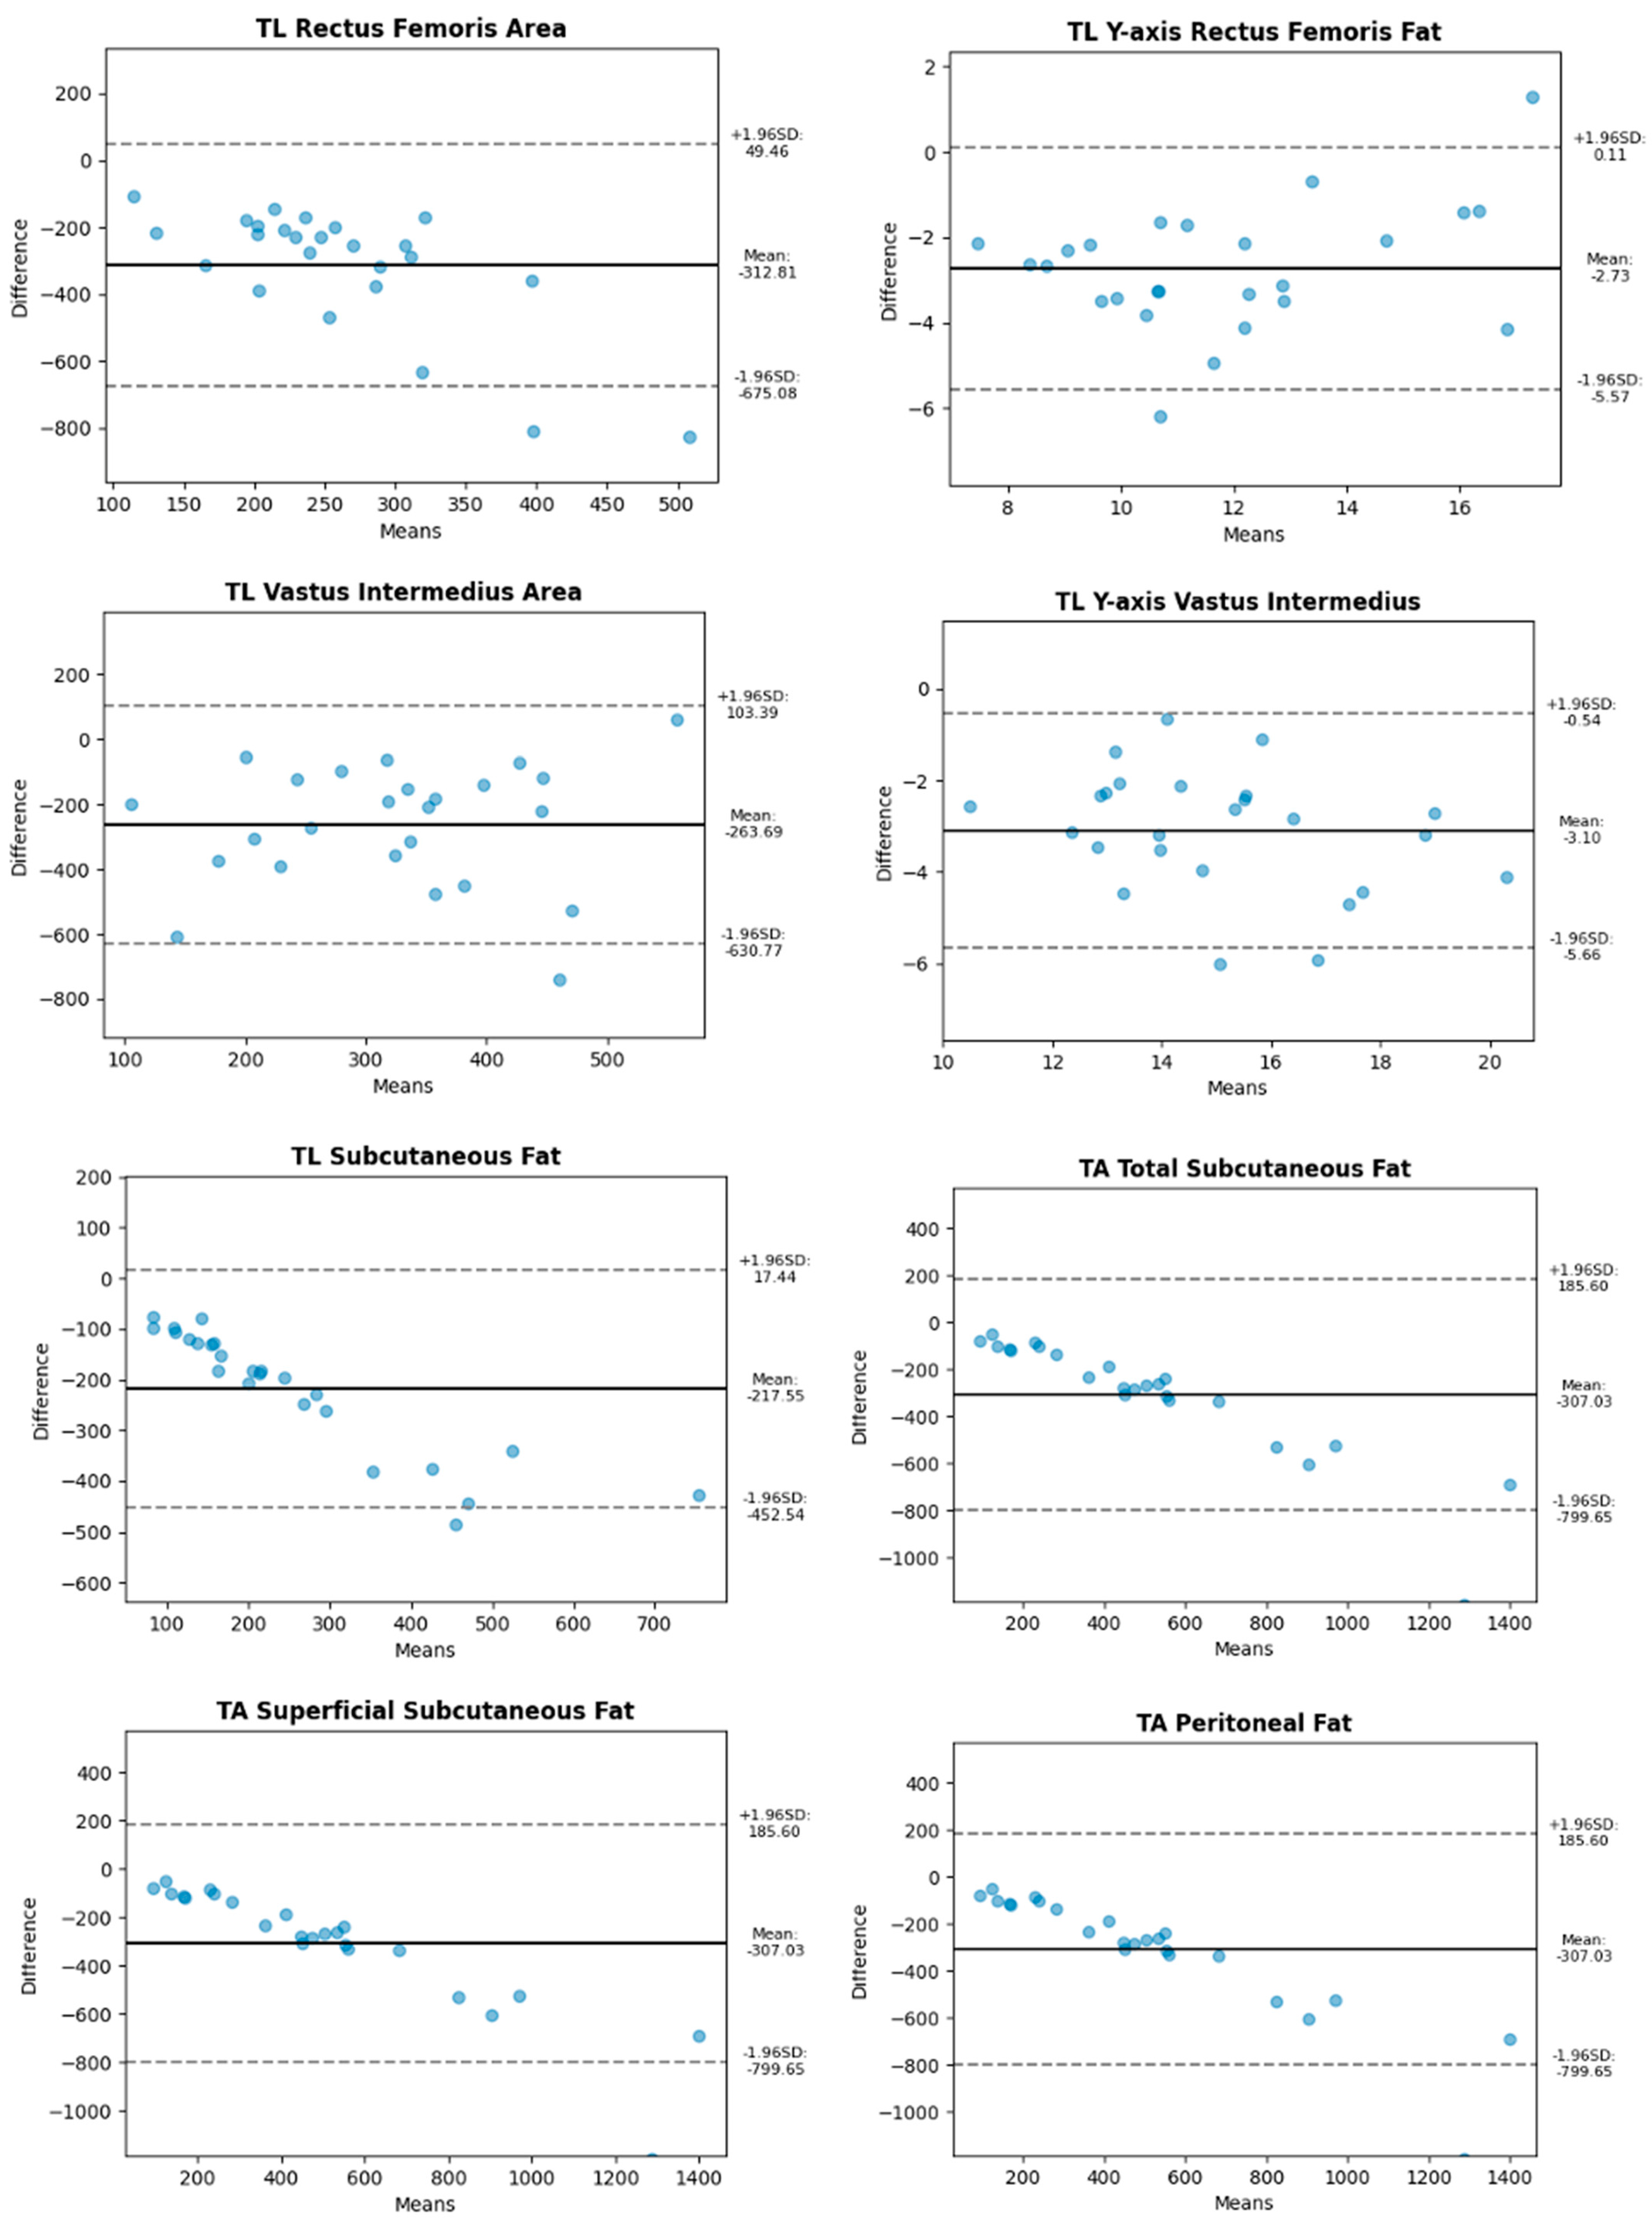

3. Results

| Abdomen | Longitudinal | Subcutaneous fat, total | 71.42 |

| Subcutaneous fat, superficial | 68.77 | ||

| Peritoneal fat | 63.0 | ||

| Transversal | Subcutaneous fat, total | 54.3 | |

| Subcutaneous fat, superficial | 55.65 | ||

| Peritoneal fat | 51.02 | ||

| Leg | Transversal | Y-axis Rectus femoris | 78.73 |

| Rectus femoris area | 28.09 | ||

| Y-axis Vastus intermediate | 81.65 | ||

| Vastus intermediate area | 43.31 | ||

| Longitudinal | Subcutaneous fat | 40.82 | |

| Y-axis Rectus femoris | 83.85 | ||

| Rectus femoris area | 46.33 | ||

| Y-axis Vastus intermediate | 81.39 | ||

| Vastus intermediate area | 36.52 |